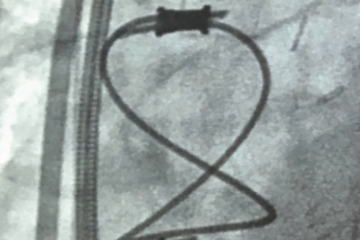

Subsequently, we attempted to selectively engage the CS ostium; however, an obstruction was encountered. An inner catheter was then used to partially engage the coronary sinus ostium, although the CS sheath could not be advanced. Angiography, via the CS sheath, revealed a subtotal occlusion and retrograde flow through what appeared to be a remnant vein of Marshall, but with a connection to the left innominate vein, consistent with a small PLSVC (Figure 2). Due to the CS ostial stenosis, the vein of Marshall or PLSVC provided venous return of the heart via its connection to the left innominate vein.

Given the subtotal occlusion, it was decided to abandon any further attempts of placement of the CS lead through the ostium. Rather, we proceeded with placement of the CS lead using the PLSVC. The previous venogram (Figure 1) demonstrated a medium to large caliber lateral vein without significant branching, which could be targeted with a quadripolar LV pacing lead. The inner catheter was utilized to subselect the PLSVC and deliver the lead into the lateral vein, which resulted in a stable lead position with adequate pacing and sensing characteristics. The greatest stability was achieved with the distal lead location within this vein. This site also provided an excellent pacing complex without diaphragmatic stimulation (Figure 4).